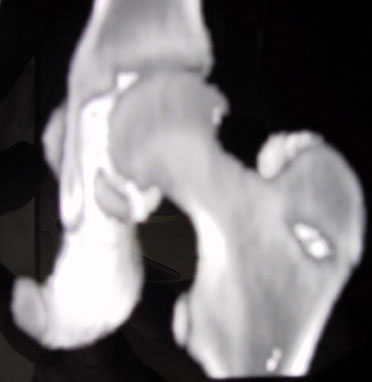

Alla TAC viene evidenziata una zona di lisi a livello del collo femorale in corrispondenza del gran trocantere.

Si segnala persistenza di ipotrofia muscolare alla coscia di sinistra. Si consiglia di eseguire scintigrafia ossea e di programmare biopsia. L'esame scintigrafico dello scheletro, eseguito dato il quesito clinico anche con tecnica trifasica e tomografica al bacino, evidenzia in fase osteotropa iperaccumulo del tracciante a gradiente piuttosto intenso in corrispondenza del gran trocantere del femore di sinistra, reperto che appare riconoscibile già nelle immagini precoci della fase dinamica e di pool ematico e che nelle immagini tomografiche interessa tutta la regione supero-laterale della porzione trocanterica del femore ed in parte il collo femorale, arrivando infero-lateralmente fin quasi al piccolo trocantere.

Tale reperto appare di non univoca interpretazione: la diagnosi di osteoma osteoide appare poco verosimile mentre ci si orienta verso una patologia tumorale di probabile natura maligna.